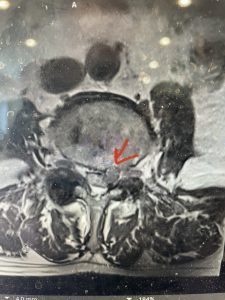

The next patient is a 71 year-old male with a two-year history of low back pain and lower extremity pain, numbness and weakness. His left leg was worse than the right. He had had five epidurals with no improvement. He also had tried physical therapy and medicines but nothing helped. He also felt that over the last three weeks he had gotten worse. He also had recently had some decreased sensation of bladder fullness and difficulty with bowel movements. MRI revealed a very tight L2-5 stenosis with an extruded L3-4 disc fragment (Fig 3).

(Figs 3a) Sagittal (a) and Axial (b) T2-weighted lumbar MRI demonstrating severe spinal stenosis L2-5 (arrow)and extruded disc at L3-4 on axial image (arrow)

He had concentric severe stenosis with severe compression of the lateral recess and foramen at L3-4 secondary to the superimposed disc herniation. The fact that he had gotten worse with subtle cauda equina features with an extremely tight canal, he underwent a decompressive laminectomy. We also augmented his laminectomy with an in situ fusion from L3-5 as he was relatively young, with more time to reform arthritis, and had been unstable enough to extrude a disc fragment. By placing “bone dust” or bone material along the sides of the spine, specifically laying it across the transverse processes after they have been drilled to bleeding bone, you provide an environment where bone formation is induced to connect the segments, stabilize them, and thereby reduce the signal to make more arthritis as that signal is still present despite the laminectomy. What was interesting was that we encountered a large extruded disk fragment that was significantly contributing to his compression which is often not found in patients in this age bracket. Post operatively he had much improvement of leg pain.